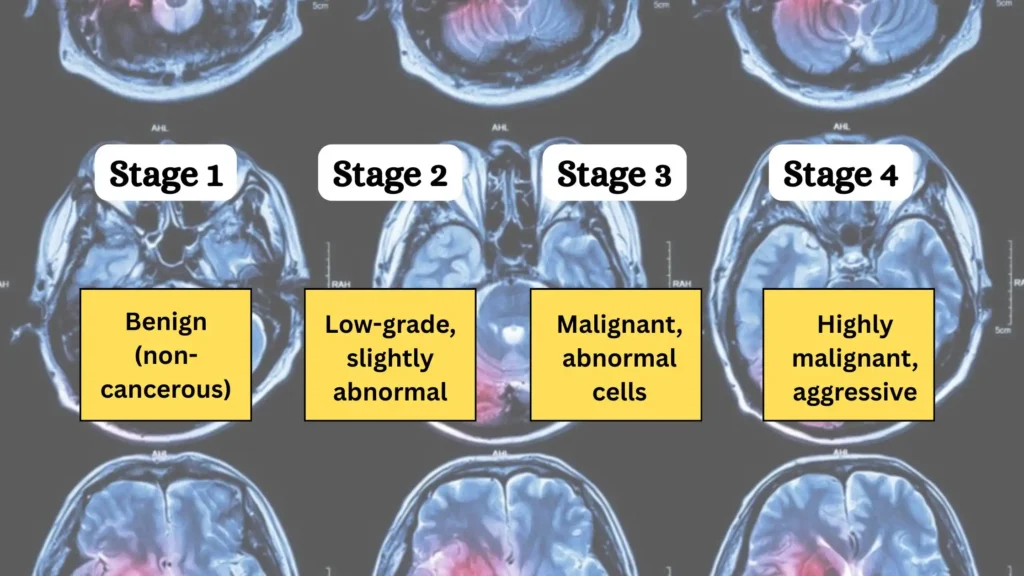

- گریدهای پایین (خوشخیم): گریدهای ۱ و ۲ معمولاً رشد آهستهتری دارند، ظاهر سلولهایشان به سلولهای طبیعی نزدیکتر است و رفتار کمتر تهاجمی دارند.

- گریدهای بالا (بدخیم): گریدهای ۳ و ۴ رشد سریع، ظاهری کاملاً غیرطبیعی و ماهیت تهاجمی دارند و به بافتهای سالم مغز نفوذ میکنند.

هر گرید نشاندهنده طیف خاصی از رفتار تومور است. در ادامه، ویژگیهای هر یک از چهار گرید به تفصیل شرح داده شده است.

گرید ۱ (Grade I): تومورهای خوشخیم با رشد بسیار آهسته

تومورهای گرید ۱ کمترین درجه بدخیمی را دارند و اغلب به عنوان تومور خوشخیم (Benign) شناخته میشوند. با این حال، واژه “خوشخیم” در مغز میتواند گمراهکننده باشد، زیرا حتی یک تومور با رشد آهسته نیز اگر در یک ناحیه حساس مغز رشد کند، میتواند با فشار آوردن به ساختارهای حیاتی، علائم جدی ایجاد کند.

- ویژگیها: سلولهای این تومورها در زیر میکروسکوپ تقریباً طبیعی به نظر میرسند و رشد بسیار کندی دارند. آنها معمولاً مرزهای بسیار مشخصی دارند و مانند یک توده مجزا رشد میکنند، نه اینکه در بافت مغز نفوذ کنند.

- درمان و پیشآگهی: اگر این تومورها در محلی قابل دسترس باشند، اغلب میتوان آنها را با جراحی به طور کامل برداشت. پیشآگهی برای تومورهای گرید ۱ عالی است و احتمال عود آنها پس از جراحی کامل بسیار پایین است و بیمار میتواند به زندگی عادی خود ادامه دهد.

- مثالها: آستروسیتوم پیلوسیتیک که در کودکان شایع است، کرانیوفارنژیوم و گانگلیوسیتوما .

گرید ۲ (Grade II): تومورهای با درجه پایین و رشد آهسته

این تومورها نیز جزو تومورهای با درجه پایین محسوب میشوند، اما یک پله از گرید ۱ تهاجمیتر هستند.

- ویژگیها: سلولها کمی غیرطبیعی به نظر میرسند و رشد آهستهای دارند. تفاوت اصلی آنها با گرید ۱ در ماهیت نفوذی آنهاست. این تومورها مرزهای مشخصی ندارند و سلولهای تومور مانند ریشههای درخت به بافتهای سالم اطراف نفوذ میکنند. این ویژگی برداشتن کامل آنها با جراحی را بسیار دشوار یا غیرممکن میکند.

- درمان و پیشآگهی: درمان اصلی معمولاً جراحی برای برداشتن حداکثر بخش ممکن از تومور است. این تومورها پتانسیل عود مجدد را دارند و متأسفانه برخی از آنها میتوانند در طول زمان دچار تحول بدخیم شده و به گریدهای بالاتر (۳ یا ۴) تبدیل شوند.

- مثالها: آستروسیتومای منتشر، IDH-جهشیافته (Diffuse Astrocytoma, IDH-mutant)، الیگودندروگلیوما (Oligodendroglioma) و اپاندیموم (Ependymoma).

گرید ۳ (Grade III): تومورهای بدخیم (آناپلاستیک) با رشد فعال

تومورهای گرید ۳ به وضوح بدخیم هستند. به آنها تومورهای آناپلاستیک نیز گفته میشود، که به معنای از دست دادن ویژگیهای سلولهای طبیعی و بالغ است.

- ویژگیها: سلولهای این تومورها به وضوح غیرطبیعی هستند و به طور فعال در حال تقسیم شدن (میتوز بالا) میباشند. آنها رشد سریعی دارند و به طور تهاجمی به بافتهای سالم مغز نفوذ میکنند. زیر میکروسکوپ، شواهدی از آتیپی قابل توجه و فعالیت میتوزی بالا دیده میشود.

- درمان و پیشآگهی: درمان این تومورها پیچیدهتر و تهاجمیتر است و تقریباً همیشه نیازمند درمانهای کمکی (Adjuvant) پس از جراحی است. این درمانها معمولاً شامل ترکیبی از رادیوتراپی (پرتودرمانی) و شیمیدرمانی میشود. احتمال عود این تومورها حتی پس از درمان کامل، بالا است.

- مثالها: آستروسیتوم آناپلاستیک، IDH-جهشیافته (Anaplastic Astrocytoma, IDH-mutant) و اپاندیموم آناپلاستیک (Anaplastic Ependymoma).

گرید ۴ (Grade IV): تومورهای بسیار بدخیم و تهاجمی

این گرید، بالاترین درجه بدخیمی را نشان میدهد. این تومورها تهاجمیترین، سریعالرشدترین و خطرناکترین نوع تومورهای مغزی اولیه هستند.

- ویژگیها: سلولها ظاهری بسیار غیرطبیعی و بدشکل دارند (آتیپی شدید). رشد آنها انفجاری و بسیار سریع است و به سرعت در سراسر مغز پخش میشوند. وجود نکروز (بافت مرده) و تکثیر عروقی از ویژگیهای بارز و مشخصه این تومورها در زیر میکروسکوپ است.

- درمان و پیشآگهی: درمان این تومورها بسیار چالشبرانگیز است. حتی با تهاجمیترین رویکردهای درمانی، ریشهکن کردن کامل آنها تقریباً غیرممکن است. هدف اصلی درمان، کاهش سرعت رشد تومور، مدیریت علائم و بهبود کیفیت زندگی بیمار است. پیشآگهی برای تومورهای گرید ۴ متأسفانه ضعیف است.

- مثال: معروفترین و شایعترین تومور گرید ۴، گلیوبلاستوما، IDH-نوع وحشی (Glioblastoma, IDH-wildtype) است. مدولوبلاستوما (Medulloblastoma) نیز که بیشتر در کودکان دیده میشود، یک تومور گرید ۴ محسوب میگردد.